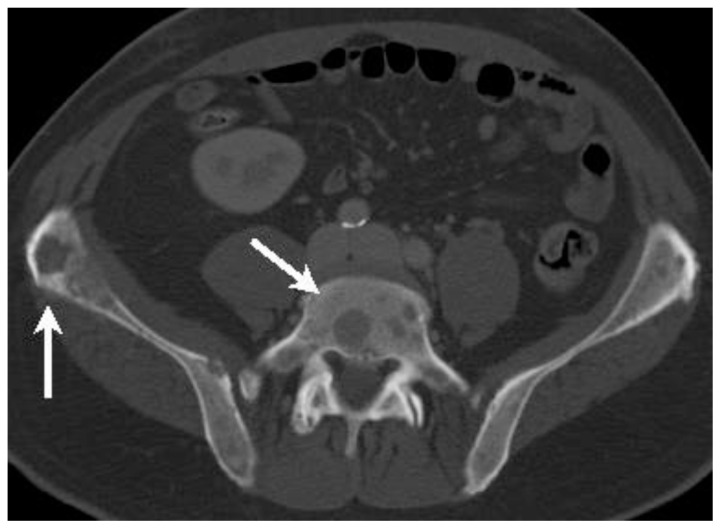

Figure 7.

58-year-old man with spinal metastases of extramammary Paget disease.

Findings: Axial enhanced CT of the pelvis in portal venous phase shows numerous predominantly lytic lesions (arrows) throughout the axial skeleton, here depicted in the L5 vertebra and iliac bones.

Technique: 120 kVp, 271 mAs, 3.0 mm slice thickness, 140 mL Iohexol 300 administered intravenously at injection rate of 4 mL/second.